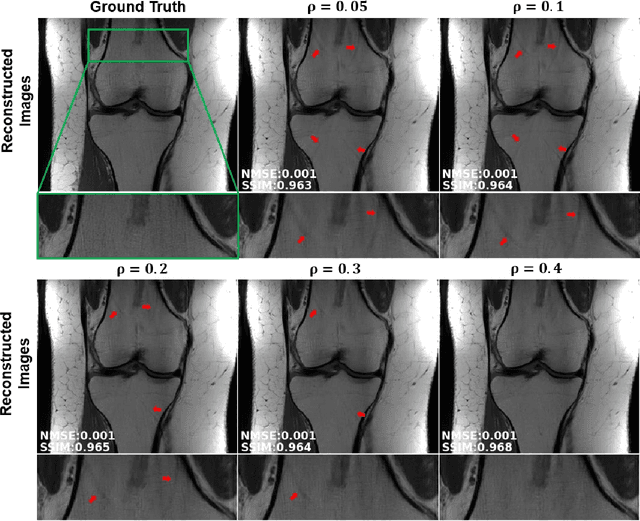

Abstract:Purpose: To develop a strategy for training a physics-driven MRI reconstruction neural network without a database of fully-sampled datasets. Theory and Methods: Self-supervised learning via data under-sampling (SSDU) for physics-based deep learning (DL) reconstruction partitions available measurements into two sets, one of which is used in the data consistency units in the unrolled network and the other is used to define the loss for training. The proposed training without fully-sampled data is compared to fully-supervised training with ground-truth data, as well as conventional compressed sensing and parallel imaging methods using the publicly available fastMRI knee database. The same physics-based neural network is used for both proposed SSDU and supervised training. The SSDU training is also applied to prospectively 2-fold accelerated high-resolution brain datasets at different acceleration rates, and compared to parallel imaging. Results: Results on five different knee sequences at acceleration rate of 4 shows that proposed self-supervised approach performs closely with supervised learning, while significantly outperforming conventional compressed sensing and parallel imaging, as characterized by quantitative metrics and a clinical reader study. The results on prospectively sub-sampled brain datasets, where supervised learning cannot be employed due to lack of ground-truth reference, show that the proposed self-supervised approach successfully perform reconstruction at high acceleration rates (4, 6 and 8). Image readings indicate improved visual reconstruction quality with the proposed approach compared to parallel imaging at acquisition acceleration. Conclusion: The proposed SSDU approach allows training of physics-based DL-MRI reconstruction without fully-sampled data, while achieving comparable results with supervised DL-MRI trained on fully-sampled data.